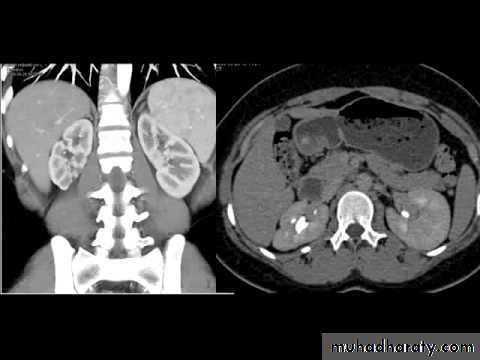

retrocaval ureter